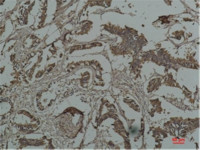

IHC-P analysis of rat lung tissue using GTX85063 PEN2 antibody.

Working concentration : 2.5 μg/ml